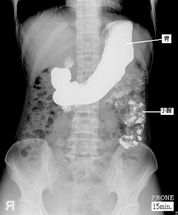

上消化道攝影是一種特殊的x光檢查,其檢查的範圍包括食道、胃、十二指腸以及其他小腸(空腸和迴腸)。

(1)當開始檢查時,會先給一小包蘇打粉,請合著一小杯的開水迅速吞下,此蘇打粉的作用是利用氣體使胃、腸道脹起來 以利觀察黏膜的情形。醫護人員會遞上一杯如奶昔般的腸胃道造影劑(鋇劑),請配合指示飲用,例如請您喝一口含在嘴巴,請您吞下時才可以吞下,檢查過程中檢查台上會開始平躺、俯臥、側躺或翻轉,有時則需要被檢查者配合閉氣,同時以X光視需要做不等次數之照相。只檢查食道、胃及十二指腸者約費時20~30分鐘,若包括空腸和迴腸者約費時2小時以上。